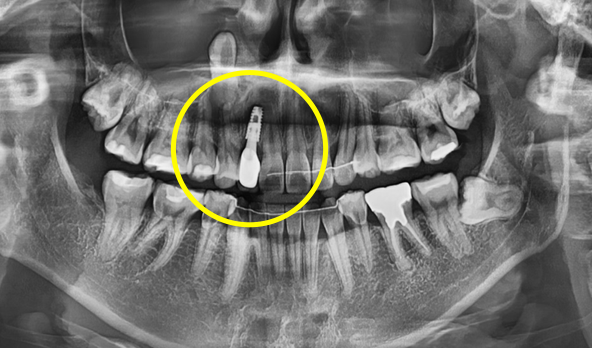

• Precise analysis of alveolar bone and nerve location via CT scan

Precise analysis of

alveolar bone & nerve location via CT scan

• 3D analysis to determine implant placement position, angulation, and depth

3D analysis to determine

implant placement position, angulation & depth